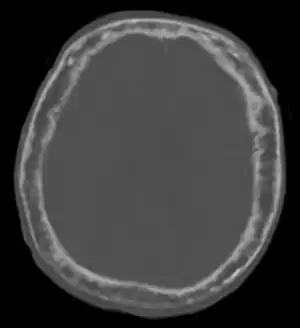

"This 92 year-old male patient presented for assessment of sudden inability to move half his body. An incidental finding was marked thickening of the calvarium. The diploic space is widened and there are ill-defined sclerotic and lucent areas throughout. The cortex is thickened and irregular. The findings probably correspond to the 'cotton wool spots' seen on plain films in the later stages of Paget’s disease."